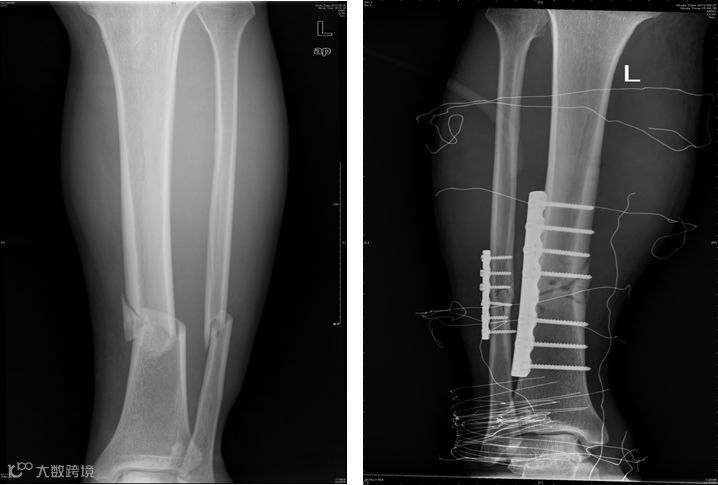

3、胫腓骨骨折

功能锻炼方法:

外固定后早期,疼痛减轻即刻进行股四头肌静止收缩运动,髌骨被动活动及足部跖趾关节和趾间关节活动。

外固定去除后,伤口愈合,可充分练习下肢各个关节活动,并逐步去拐行走。

增加髋、膝、踝关节活动练习,可做起立与坐下练习,健肢站立,患肢做髋屈伸、内收。